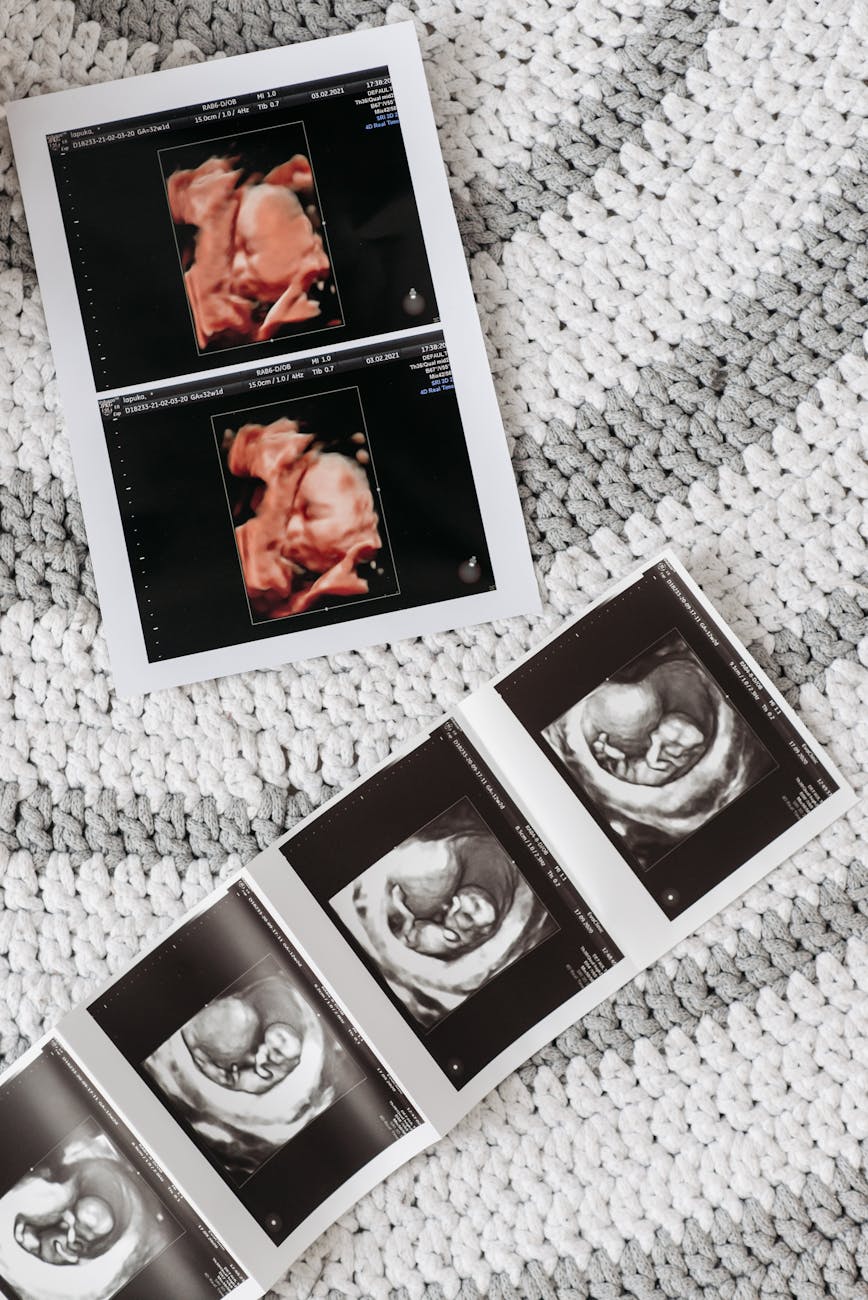

Biologically speaking, before you became who you are, you were a zygote—a single fertilized cell with mind-bending potential. Soon afterwards – within a matter of hours – you were a morula (Latin for “mulberry”). A morula is comprised of 60 or more cells, all lumped together. At this point in your biological development, you looked like a microscopic mulberry. Your biological potential, originally housed in the DNA of parental gametes, was still unthinkably vast, yet slightly reduced.

By about five days into your biological journey, you became a blastocyst. At this point, you were comprised of something like 150 cells. At each stage of development, you became bigger and better defined, but always at the cost of potentiality. You started with the potential to be anyone within the confines of the DNA in your cell. Since there are 3.2 billion nucleotide pairs on our chromosomes (humans have 46 of them), and every one of those pairs can combine in four possible ways, that is a lot of potential. By day 5, the billions of different versions of you that had been possible had decreased. You were on your way to becoming yourself.

You were an embryo before you knew it—quite literally. Significant development occurred during the embryonic phase, which means that your potential (though still vast) has been further narrowed. Nine weeks in and you are a fetus. You’re beginning to look like a human being and even like a particular human being, but advances in development always comes at the cost of diminishing potential.

By the time you were born, your biological potential (for example, the color of your eyes, the shape of your face, the complexion of your skin, your body type) was narrower than it was when you were a morula. With each step of development, the breadth of potentiality is diminished. In return for this expenditure of potential, you became more substantially (and not just potentially) yourself.